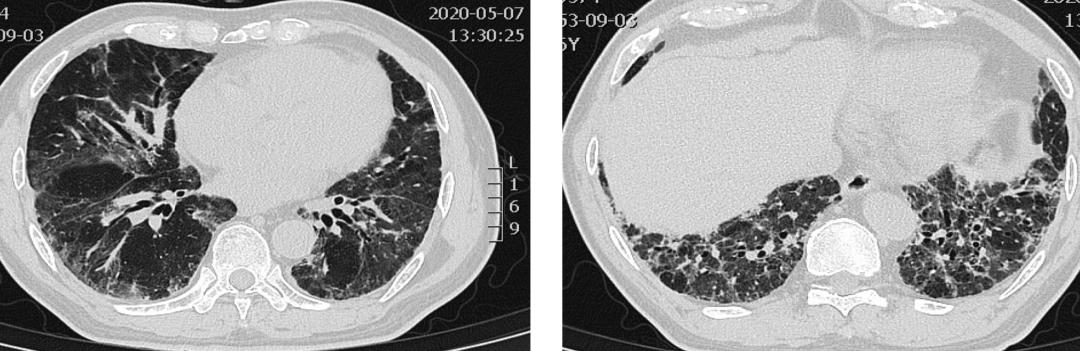

【图3】甲强龙120mg-80mg 治疗后7天CT。双肺磨玻璃渗出明显减少,纤维条索影增多。

【图4】吡啡尼酮200mg tid+美卓乐32mg qd+他克莫司1mg bid 2周后CT。双肺磨玻璃渗出明显减少,纤维条索影减少小叶间隔增厚明显改善。